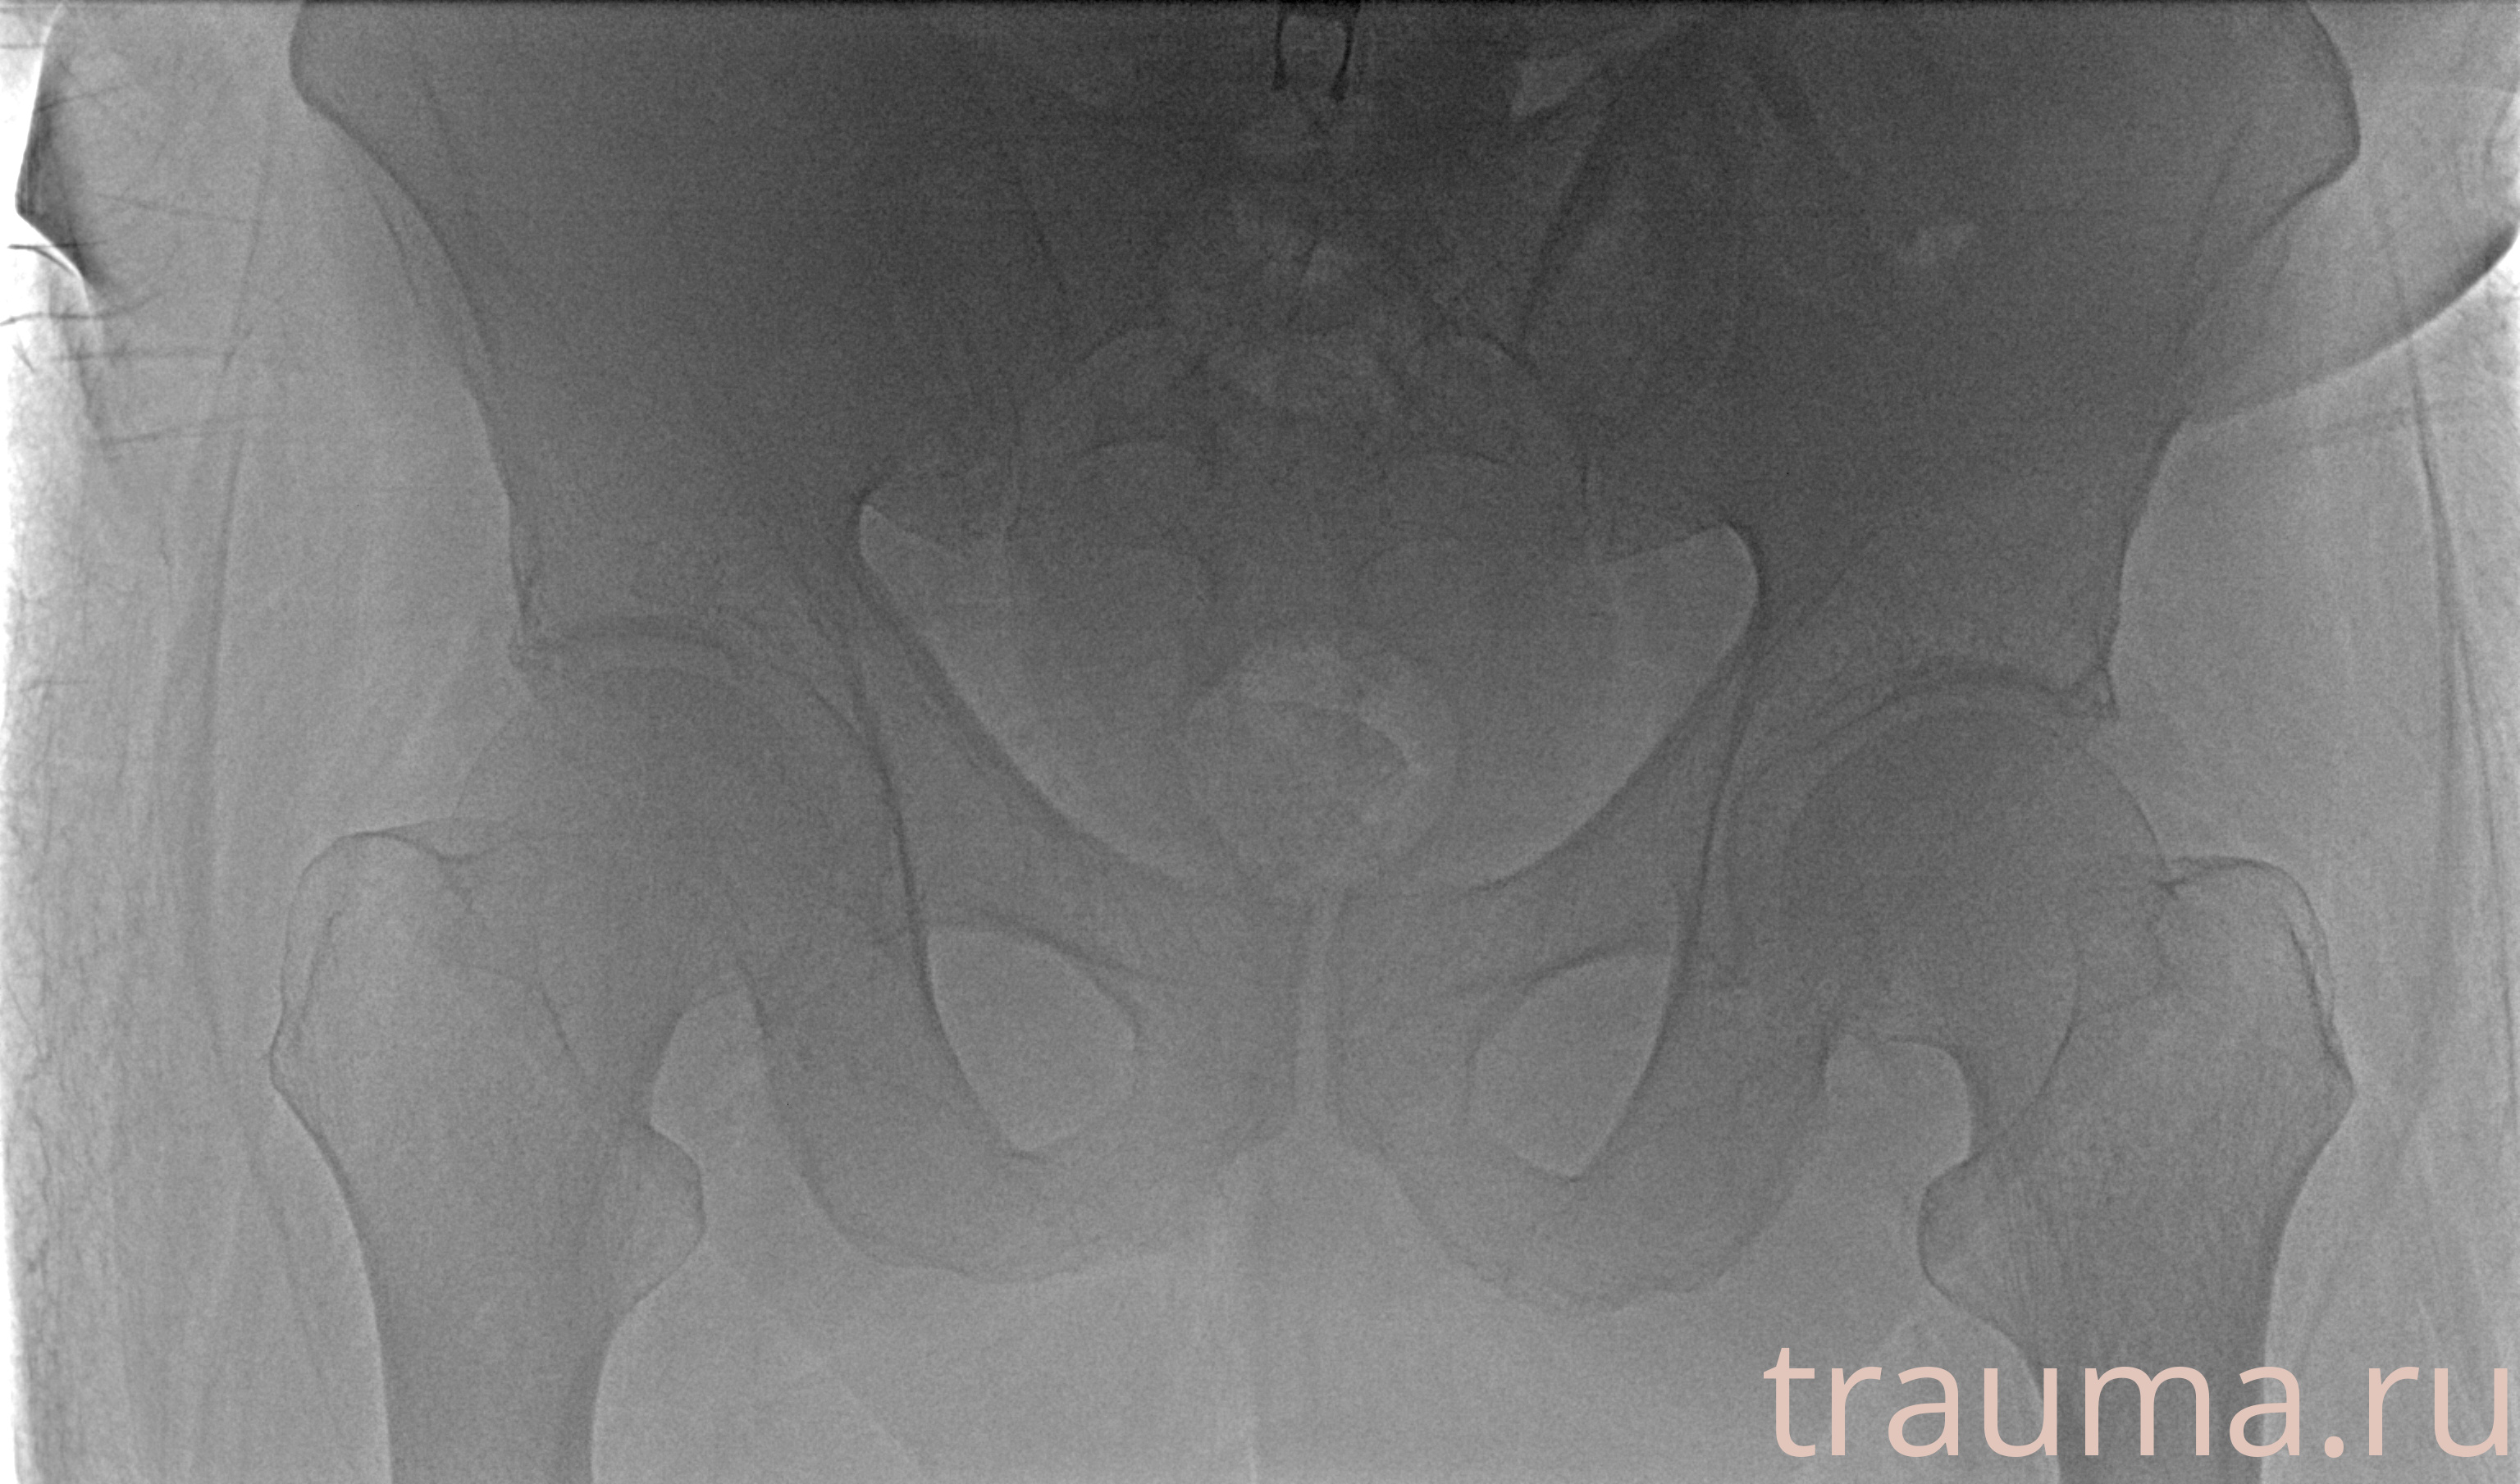

Рентген на дому: по вашему адресу приезжает врач-рентгенолог, травматолог-ортопед с мобильным рентгеновским аппаратом, проводит диагностику травмы или заболевания, делает необходимые рентгенограммы, дает рекомендации по дальнейшему лечению. Получить качественные снимки в домашних условиях возможно благодаря уникальной методике, разработанной МосРентген Центром для института  Склифосовского